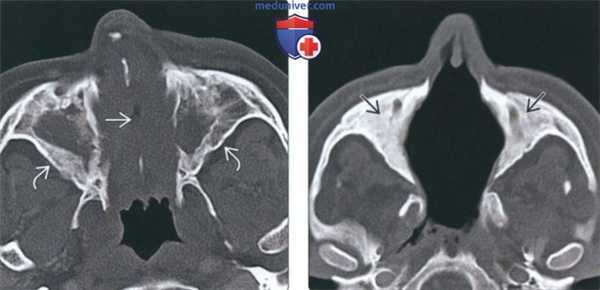

(Слева) На корональной МРТ (Т1 ВИ) у пациента с ГПА определяется одноаороннее поражение правой верхнечелюстной пазухи. Патологическое содержимое распространяется из просвета пазухи в жевательное пространаво. Обратите внимание на замещение нормального «жирового» сигнала за пазухой справа и сравните с неизмененной левой стороной.

(Справа) На аксиальной МРТ (Т1ВИ FS) у этого же пациента определяется контрастирование патологических мягких тканей позади пазухи и в крылонебной ямке. Обратите внимание на подавление сигнала в жировой клетчатке слева (норма).